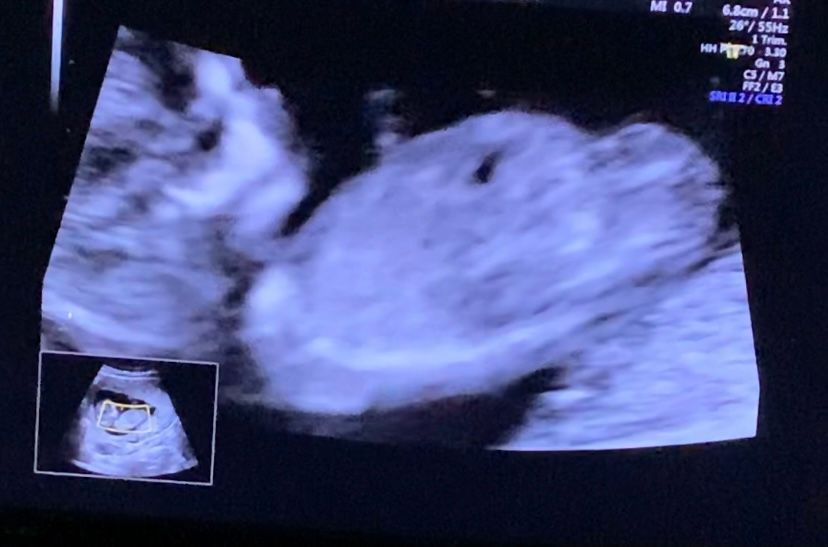

Девочки , мальчик или девочка?

12 Недель , сказали половой бугорок кверху , посмотрите пожалуйста :)

Не знаю, где тут что кверху, а вот то, что к нам попкой больше, это да. В общем, не видно

У меня был вверх в 13 недель. Говорили 90% мальчик. В итоге девочка) похожи наши бугорки

Мне тоже предположили мальчика☺️ Остаётся ждать второго узи. С мальчиками реже ошибаются.

😂😂😂 мне кажется, на последнем фото в уголке фигура из 3х пальцев . Вообще кверху парень, а девочка- он параллелен тельцу. Но это же опять из теории и прочитанного.